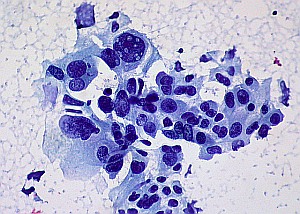

Krebszellen: Genom könnte Schätze enthalten. Bild: Flickr/Uthman